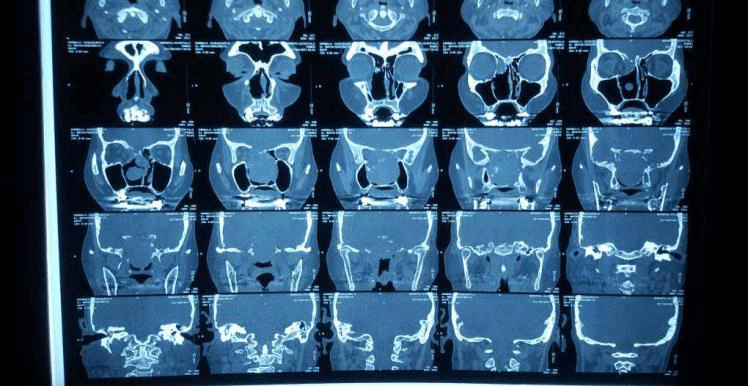

2012 সালের অক্টোবরে তিনি আমাদের কাছে ফিরে এসেছিলেন, ধীরে ধীরে প্রগতিশীল ডান-পার্শ্বযুক্ত নাক ব্লক, ফুসফুস অনুনাসিক স্রাব এবং মাঝে মাঝে 2-বছরের মাথাব্যথার অভিযোগ করেছিলেন। এপিস্ট্যাক্সিস বা অন্যান্য ইএনটি অভিযোগের কোন ইতিহাস ছিল না। পরীক্ষায়, নাকের ডান দিকে মসৃণ পৃষ্ঠ ভরাট করে একটি বড় ভর ছিল, স্পর্শে রক্তপাত হয়নি। এবং একটি স্থূল DNS বাম. মস্তিষ্কের এমআরআইতে দেখা গেছে যে একটি মিশ্র তীব্র ক্ষত মাথার খুলির স্ফেনয়েড, ইথময়েড সাইনাস এবং সেলা এবং ক্লিভাসের অংশে অনুপ্রবেশ করে। সমস্ত রুটিন রক্ত এবং প্রস্রাব তদন্ত স্বাভাবিক ছিল. ক্ষতের বায়োপসি ইনভার্টেড প্যাপিলোমার পুনরাবৃত্তির পরামর্শ দিয়েছে। তিনি টিউমারের এন্ডোস্কোপিক ডিবুলিং করান। HPE এই সময় hemangiopericytoma পরামর্শ ছিল.

তিনি প্রথমে যশোদা হাসপাতালে ওপি হিসাবে এবং পরে স্থানীয় ইএনটি-এর সাথে অনুসরণ করেছিলেন। দুই বছর পর তার আমাদের সফরের সময় পুনরাবৃত্তির কোনো প্রমাণ পাওয়া যায়নি। এখন তিনি এপ্রিল মাসে আমাদের কাছে উপস্থাপন করেছিলেন যে এক সপ্তাহের জন্য ডান দিকের নাক দিয়ে রক্তপাত হচ্ছে। DNE ডানদিকে একটি অনিয়মিত মসৃণ পৃষ্ঠ ভাস্কুলার ভর দেখিয়েছে। CT PNS অনুনাসিক গহ্বরের পিছনের অংশে নরম টিস্যু ভর দেখায় যা ছাদ পর্যন্ত প্রসারিত হয় (ক্রিব্রিফর্ম প্লেট) এবং উপরে স্ফেনয়েড সাইনাস এবং নীচে নাসোফ্যারিনক্স পূরণ করে। তাকে রেডিওথেরাপি বিভাগে রেফার করা হয়েছিল যেখানে তাকে মস্তিষ্ক এবং কক্ষপথের নৈকট্যের কারণে IMRT-এর পরামর্শ দেওয়া হয়েছিল।